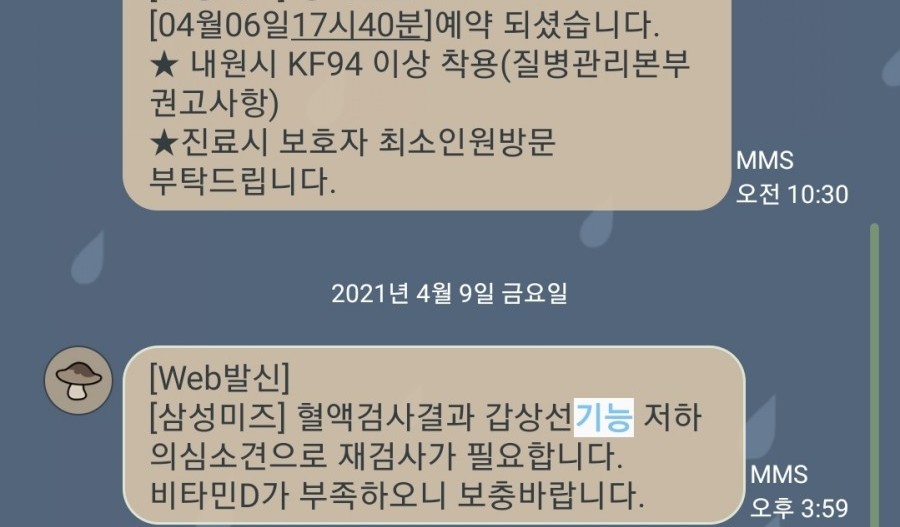

심장 소리를 듣고 산전 검사를 했다.

첫 번째 검사는 갑상선 기능 저하가 의심되는 소견으로 재검사가 이루어졌으며 두 번째 갑상선 혈액검사 결과 정상으로 나왔다. 휴대약을 꾸준히 먹고 있는 상태라 정상적으로 나오지만 간혹 수치가 떨어지기 때문에 여전히 주기적인 검사를 하고 있다.